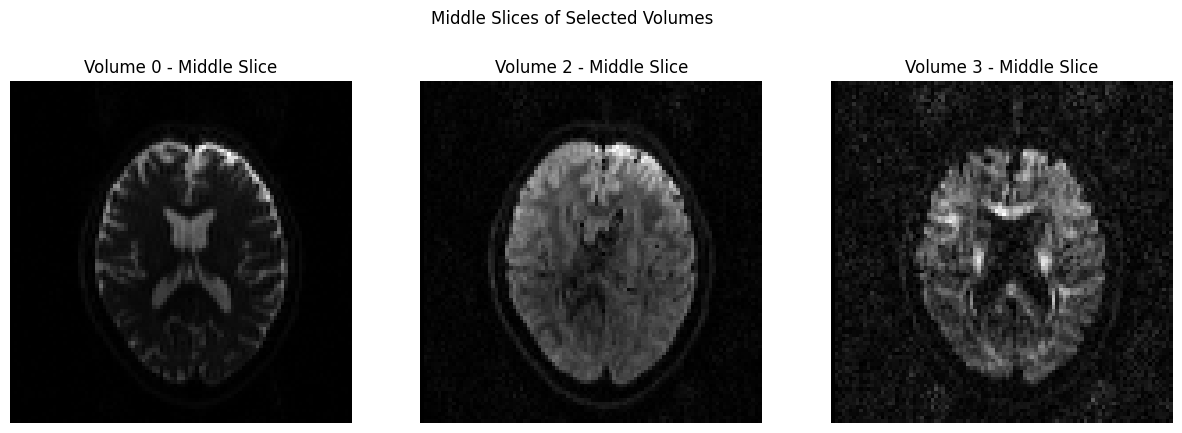

In order to view the image, we will use a couple of different packages, and you can determine which one you prefer. The first one we will use it matplotlib, which was loaded earlier in this notebook. In the code below, we will temporarily convert the data to NIFTI format and plot 3 volumes with Matplotlib.

dwi_file = 'sub-CON02_ses-preop_acq-AP_dwi.nii.gz'

# Load the NIfTI file

nii_image = nib.load(dwi_file)

data = nii_image.get_fdata()

# Define volume indices for the three volumes you want to display

volume_indices = [0, 2, 3]

slice_index = data.shape[2] // 2 # Choose the middle slice for visualization

fig, axes = plt.subplots(1, 3, figsize=(15, 5))

for i, vol_idx in enumerate(volume_indices):

# Extract the middle slice from the selected volume and rotate it 90°

rotated_slice = np.rot90(data[:, :, slice_index, vol_idx])

axes[i].imshow(rotated_slice, cmap="gray")

axes[i].set_title(f"Volume {vol_idx} - Middle Slice")

axes[i].axis("off")

plt.suptitle("Middle Slices of Selected Volumes")

plt.show()